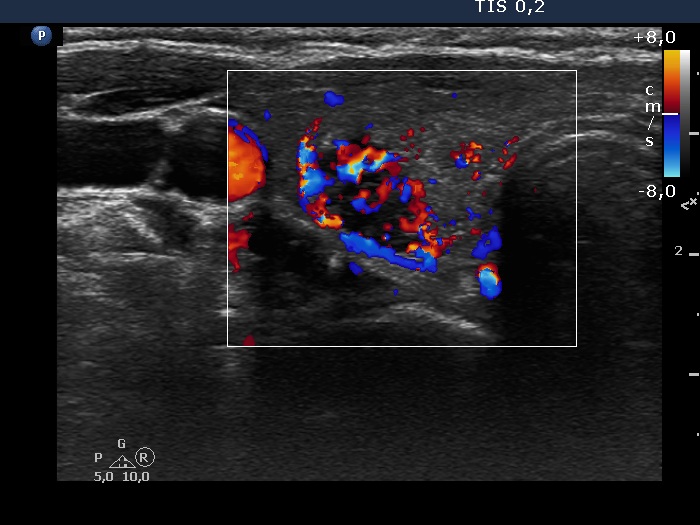

100 consecutive cases of papillary cancer - case 078 (ultrasonographic picture 5)

Right lobe, longitudinal scan

Right lobe, transverse scan, color Doppler mode. This is a chaotic intranodular pattern.